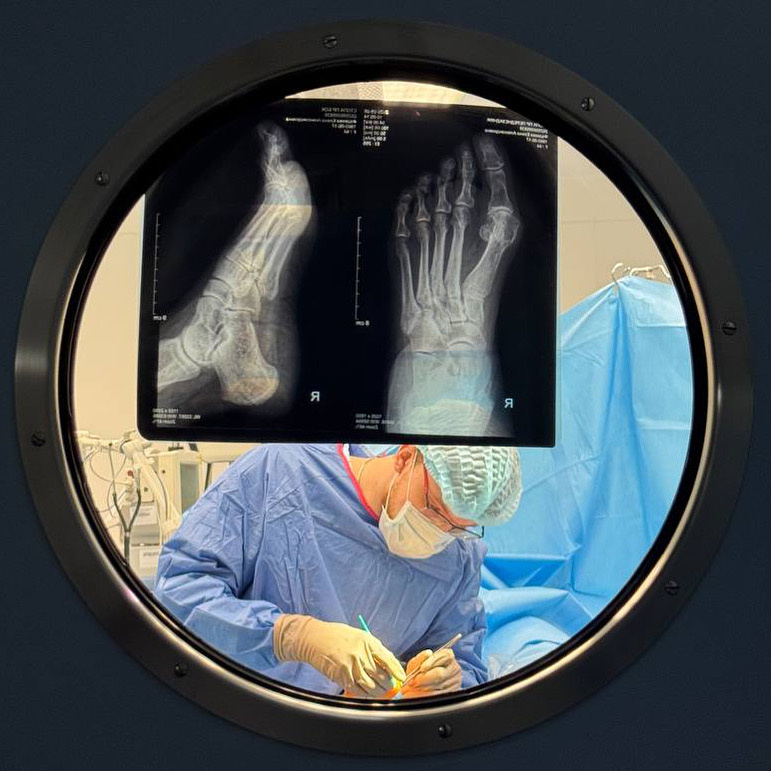

Следует помнить, что только травматолог-ортопед сможет правильно поставить диагноз и индивидуально подобрать лечение.